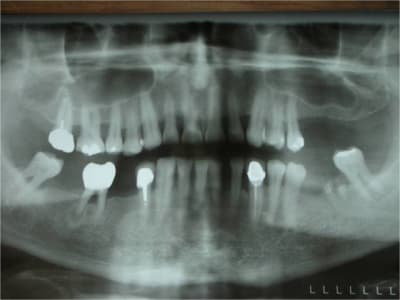

bon, comme dans le titre, une petite ROG avec pose de 3 leone (un 4.1/12 en 24, 4.1/8 en 25 et un 6.5/5 en 26)

pose de 3 cap de 1.5mm permettant de faire piquet de tente pour la rog réalisée avec du kasios et une membrane collagène AT de 22x22mm

sincèrement, j'aurais pas eu un implant court de 6.5mm planté dans à peine 3/4mm d'os, j'aurais fait un bridge entre 14 et 16...

à giantcoco, dans ton étude y figure ce genre de cas? ou c'est des implants courts totalement enfouis dans l'os?

là le cumul des risques m'a fait préférer bétonner en posant 3 implants et ce d'autant plus que j'avais largement la place

pour ce qui est de nombre d'implant je l'aurais abordé comme toi mais j'aurais plus certainement cherché a gagner de l'os au niveau du sinus (le rapport implant/couronne ne semble pas poser problème).

oui, mais t'as pas vu l'image dans le sinus?

l'orl ne veux pour l'instant pas y toucher mais j'avais son feu vert si pas de soulevé...et comme il y avait un défaut horizontal...et bien ROG...;-)